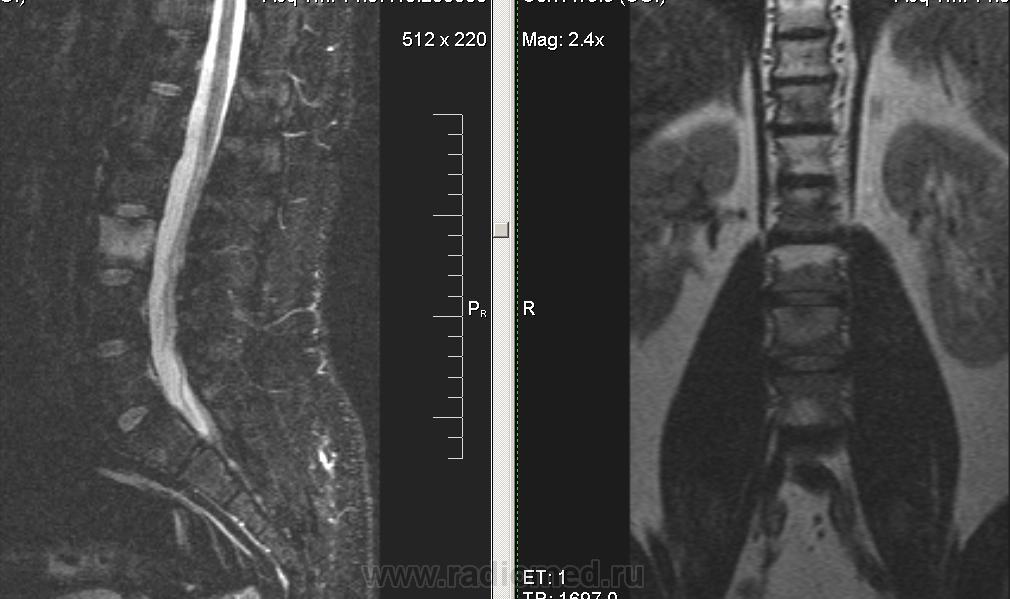

То же самое + крестцово-подвздошные сочленения.

Сакроилеит. Так что спондилоартрит наиболее вероятен. И боль в правой ноге понятна. Я если у молодых людей причины для корешковых болей не вижу, делаю программу на крестцово-подвздошные суставы. Единственно, в позвоночнике обычно бывает отёк костного мозга апофизов, дугоотростчатых и рёберно-позвонковых суставов.